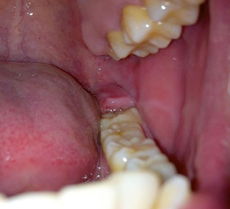

当你吞咽时感觉到喉咙里有异物感,通常是指喉咙后壁或扁桃体区域有肿胀或突出的感觉,这种感觉可能是由于以下几种原因引起的:

- 咽后壁淋巴组织增生:这是最常见的原因之一,咽后壁的淋巴组织在受到刺激或感染时会增生,形成类似“肉坨”的感觉,这种情况通常与慢性咽炎、过敏或胃酸反流有关。

- 扁桃体肿大:扁桃体是免疫系统的重要组成部分,当身体受到感染时,扁桃体会肿大,导致喉咙里有异物感。

- 咽部囊肿或息肉:虽然相对少见,但咽部囊肿或息肉也可能导致吞咽时有异物感,这些通常是良性的,但需要及时处理。